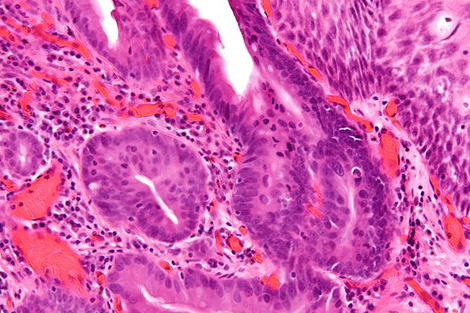

A team led by biophysicist Peter Weightman uses the ALICE accelerator at England’s Daresbury Lab to image the biochemical composition of tissue from patients afflicted by a condition called Barrett’s esophagus. Barrett’s sufferers are 10 times more likely to develop esophageal cancer, but most acquire symptoms too late for treatment.

With ALICE-created images, doctors can distinguish pre-cancerous tissues from benign ones. The method may one day give diagnoses in time to save lives.

Doctors currently diagnose pre-cancerous tissues in patients with Barrett’s esophagus by analyzing random cell samples. This technique can miss areas with telltale changes, says University of Liverpool gastroenterologist Mark Pritchard, who works on Weightman’s team. If the new technology is shown to be accurate and reliable, it could give doctors a more comprehensive view.

To measure cancer cues, scientists tune the ALICE accelerator’s infrared light to a wavelength that excites one specific type of cellular component, such as DNA or proteins. When the light shines into the sample, the excited electrons from that component lose their energy in the form of photons—light researchers can see. They collect this reflected light with a micron-wide tube that they spend about an hour scanning slowly over the entire tissue surface. The result is a map of the density of one component, such as DNA, across the sample.

For each sample, the researchers repeat the process to map three or four different components known to vary in cancerous versus noncancerous tissues. “When you go cancerous, the DNA goes up and the protein goes down,” Weightman says. That’s because cancer cells have more active DNA than healthy ones, facilitating the cell growth and DNA duplication necessary for a tumor to form.

So far, scientists have looked at two biopsy samples in a blind test and have proven their ability to correctly distinguish cancerous from non-cancerous tissue. They are still honing their methods; perhaps a certain level of one protein will prove to be the disease’s key signature, Weightman says.